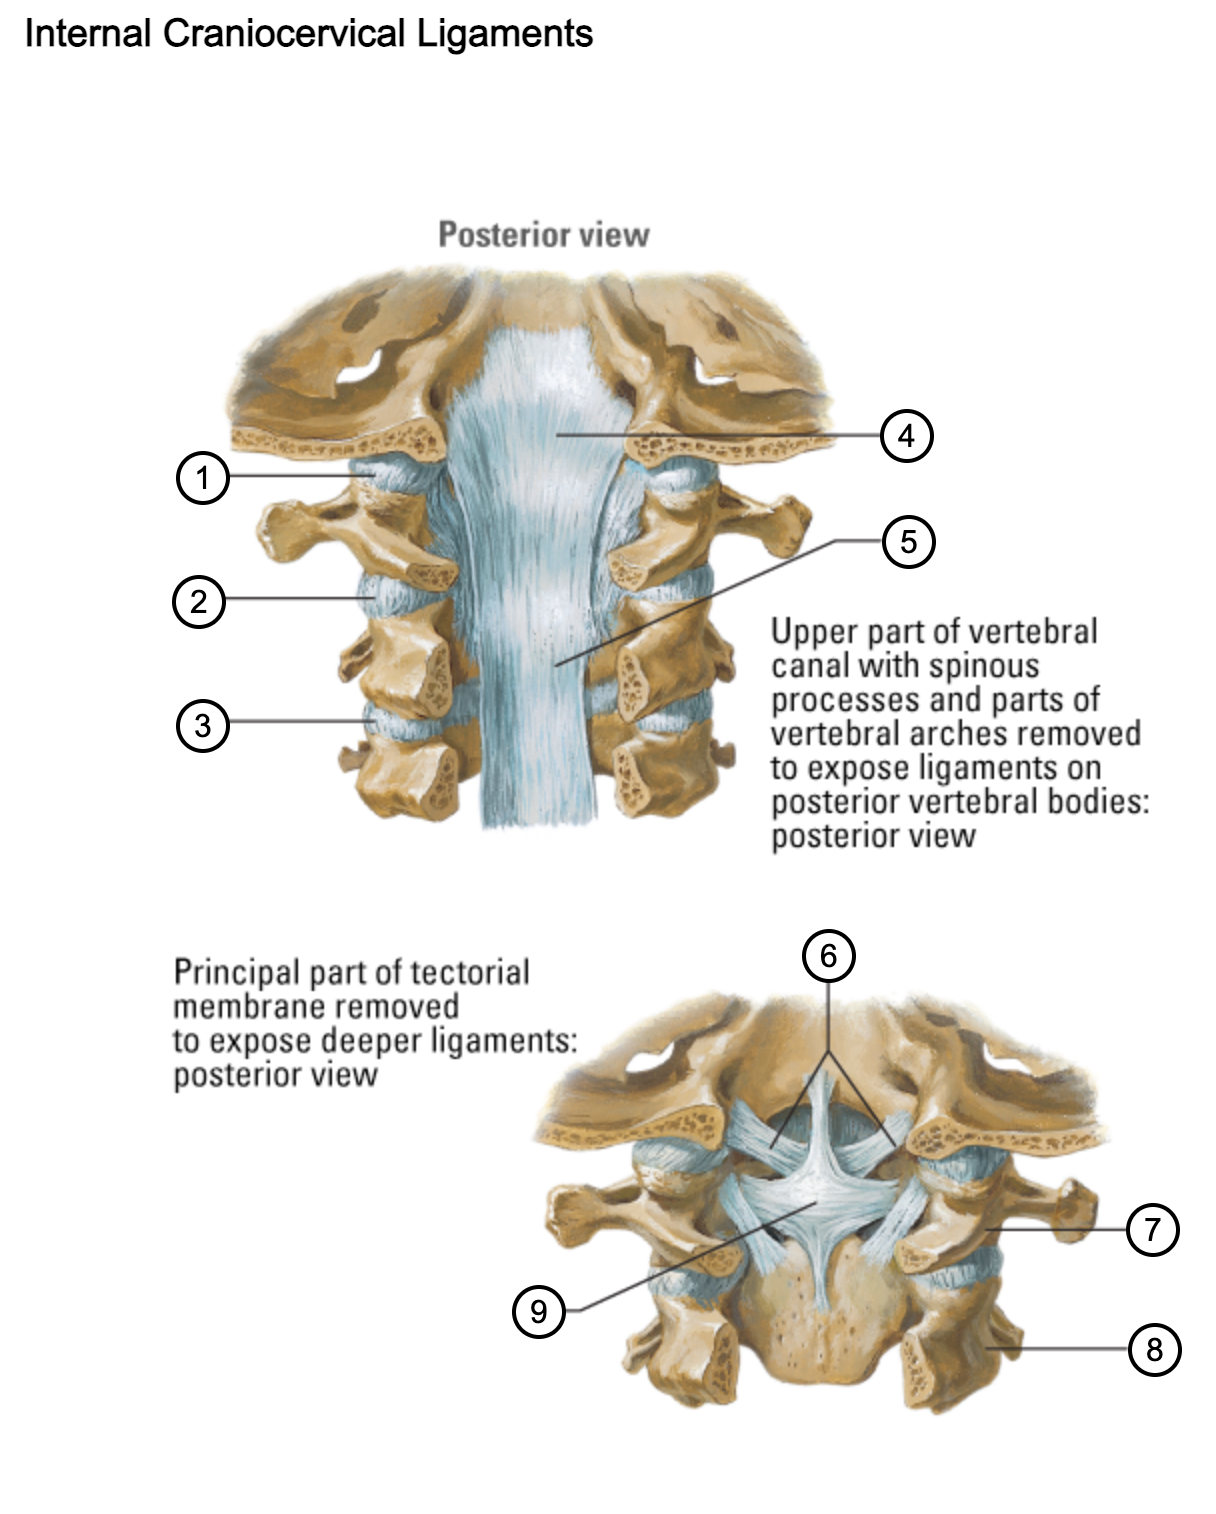

1

capsule of atlantooccipital joint

2

capsule of lateral atlantoaxial joint

3

capsule of zygapophysial joint (between axis and C3 vertebra)

4

tectorial membrane of cervical vertebral column

5

posterior longitudinal ligament

6

alar ligaments

7

atlas (C1)

8

axis (C2)

9

cruciform ligament (superior longitudinal band; transverse ligament of atlas; inferior longitudinal band)